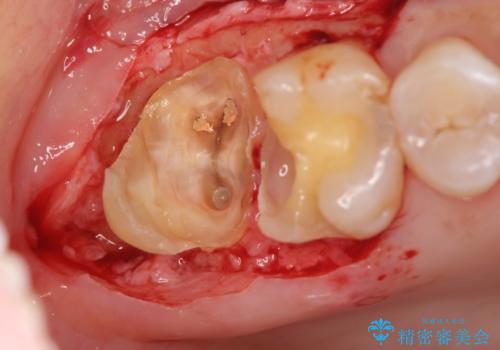

歯髄方向 歯肉方向へと深い 2種類の大きな虫歯

- 他院で虫歯が大きすぎて歯を抜くしかないと言われ、歯を残す手段はないものかと当院へ初診来院されました。

#17は失活歯で歯肉方向への縁下カリエス、#16は生活歯であるものの歯髄ギリギリの処置となるであろうとが予想される治療です。

歯周外科、マイクロスコープを用いた虫歯治療を行い歯を残す治療計画を立てます。

深い虫歯には歯周外科、マイクロスコープを用いた丁寧な虫歯の除去を行うことで歯の神経や歯そのものを残すことが可能になります。